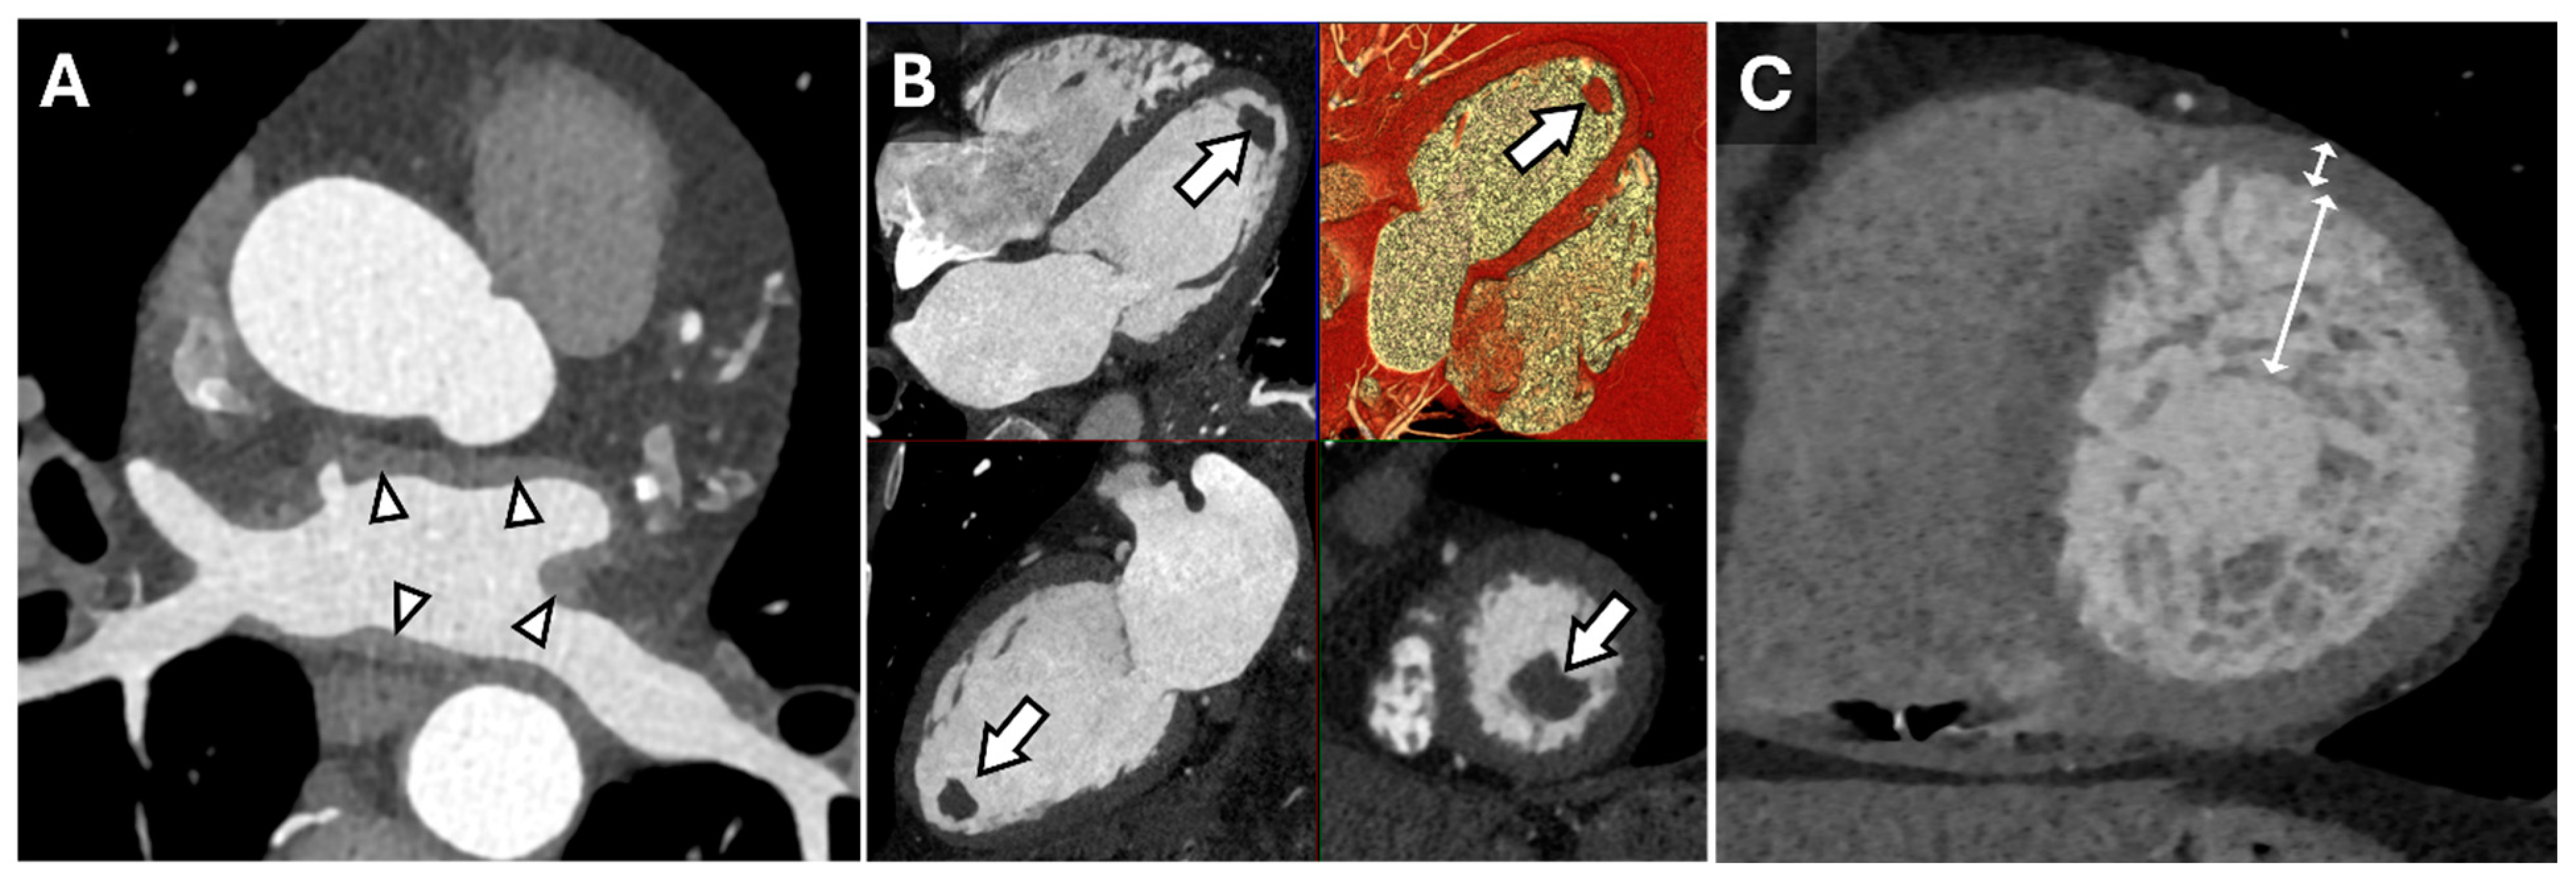

5. Ischemic Evaluation

- Vliegenthart, R.; Henzler, T.; Moscariello, A.; Ruzsics, B.; Bastarrika, G.; Oudkerk, M.; Schoepf, U.J. CT of coronary heart disease: Part 1, CT of myocardial infarction, ischemia, and viability. AJR Am. J. Roentgenol. 2012, 198, 531–547. [Google Scholar] [CrossRef]

- Nagao, M.; Matsuoka, H.; Kawakami, H.; Higashino, H.; Mochizuki, T.; Murase, K.; Uemura, M. Quantification of myocardial perfusion by contrast-enhanced 64-MDCT: Characterization of ischemic myocardium. AJR Am. J. Roentgenol. 2008, 191, 19–25. [Google Scholar] [CrossRef]